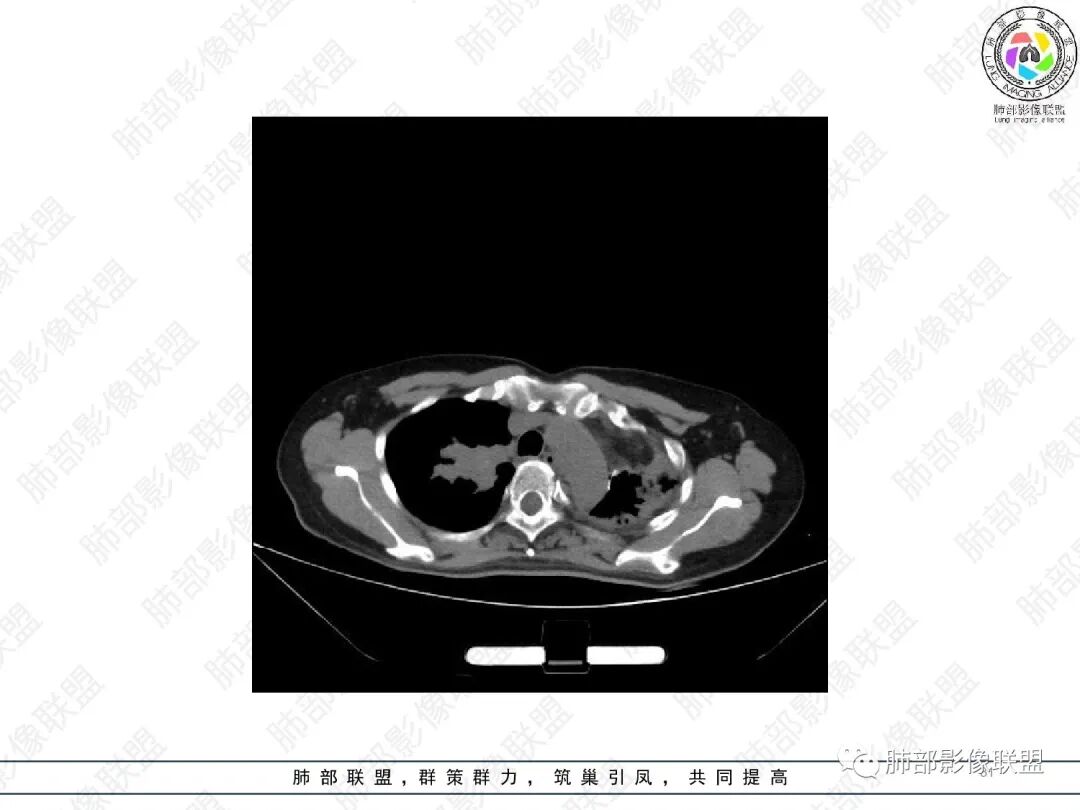

1.中年女性,主因“咳嗽、咳痰半年余”入院,既往史:8年前因左肺病在外院变行左肺叶切除术,诉术后抗结核治疗1年,具体病理等不详。实验室IGE显著增高。

2.胸部CT:右肺上叶及中叶不规则块状影,沿支气管走行方向指套样影,支气阻塞湖嵌塞,腔内可见高密度影。灶周可见磨玻璃,外围见结节影及树芽征。左肺体积缩小,见不规则条索影、胸膜增厚,纵隔牵拉左移。